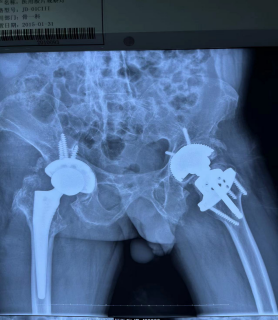

经检查发现,何先生在14年前的髋关节置换手术后,双侧髋关节周围不但软组织粘连严重,增生的骨赘就像一把把利刃扎在他的关节旁边,经过14年的使用和磨损,髋臼假体边缘发生了囊状改变,髋关节假体已经松动了。“患有先天性强直性脊柱炎的患者,最怕就是髋关节疾患产生,85%以上的强直性脊柱炎患者出现残疾就是因为髋关节病变造成的,髋关节置换手术是治疗髋关节疾患的重要手术方式,而术后人工关节松动、假体周围骨折、感染等情况对于强直性脊柱炎患者也比较常见,这时候常常采用考虑人工髋关节翻修手术治疗。”骨一科主任唐新文介绍,“人工髋关节翻修术,可以说是骨科难度较大,风险较高的手术之一,简单地说就是将原来松动的人工关节或假体周围骨折、感染的关节取出来,重新置入一个新的关节,从而改善患者的疼痛及功能状态,手术过程非常复杂,再加上何先生是一名先天性强直性脊柱炎患者,更为手术增加了风险。”

8月3日,在医务人员的精心安排下,何先生经由鼻腔行特殊性全麻后,顺利接受了右侧髋关节置换术后假体松动翻修术,手术团队小心翼翼地将髋关节假体取出,仔细松解和清除了局部粘连的软组织及增生的骨赘,准确找到适应何先生髋关节外展、前倾的角度,重新植入新的假体。手术过程非常顺利,术后患者右髋关节处疼痛明显缓解,右髋关节活动较术前得到很大程度上的改善,何先生感到非常高兴。9月5日,何先生再次接受了左侧髋关节置换术后假体松动翻修术。